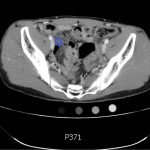

The CT abdomen/pelvis with intravenous contrast shows a dilated appendix (see red outline) with thickened, hyperenhancing wall (see blue outline) best visualized in the axial and coronal planes.